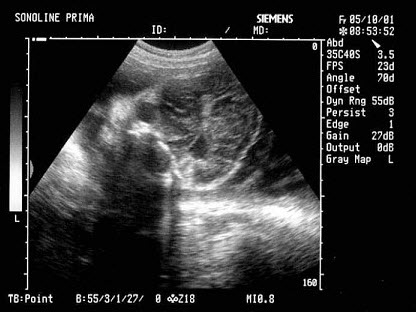

53、单项选择题

根据超声声像图,提示结构为()

A.脐带

B.胎盘

C.胎儿躯干

D.胎儿臀部

E.子宫肌层